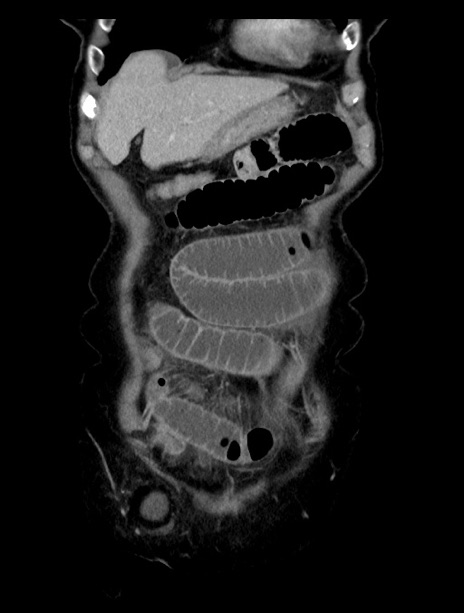

症例23(冠状断像)

【症例】70歳代女性

【主訴】下腹部痛・嘔吐

【現病歴】2日前より腹痛あり。昨日嘔吐あり。症状改善しないため来院。

【既往歴】胃GISTに対して胃部分切除後。

【身体所見】BT 37.1℃、BP 128/77mmHg、腹部:平坦・軟、下腹部に圧痛あり。

【データ】WBC 10200、CRP 0.31